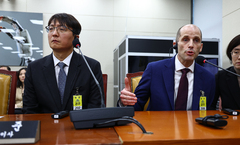

![[서울=뉴시스] 미국 콜로라도대 암센터 폐암 프로그램을 이끄는 로스 카미지(58) 박사가 폐암 진단을 받은 사실을 뒤늦게 공개했다. 사진은 카미지 박사의 모습. (사진 = CBS콜로라도 캡처) 2025.09.30. *재판매 및 DB 금지](https://img1.newsis.com/2025/09/30/NISI20250930_0001957904_web.jpg?rnd=20250930141951)

[서울=뉴시스] 미국 콜로라도대 암센터 폐암 프로그램을 이끄는 로스 카미지(58) 박사가 폐암 진단을 받은 사실을 뒤늦게 공개했다. 사진은 카미지 박사의 모습. (사진 = CBS콜로라도 캡처) 2025.09.30. *재판매 및 DB 금지

23일(현지시각) 미국 매체 CBS 콜로라도는 미국 콜로라도대 암센터 폐암 프로그램을 이끄는 로스 카미지(58) 박사가 "3년 전 폐암 진단을 받았다"며 투병 사실을 공개했다고 보도했다.